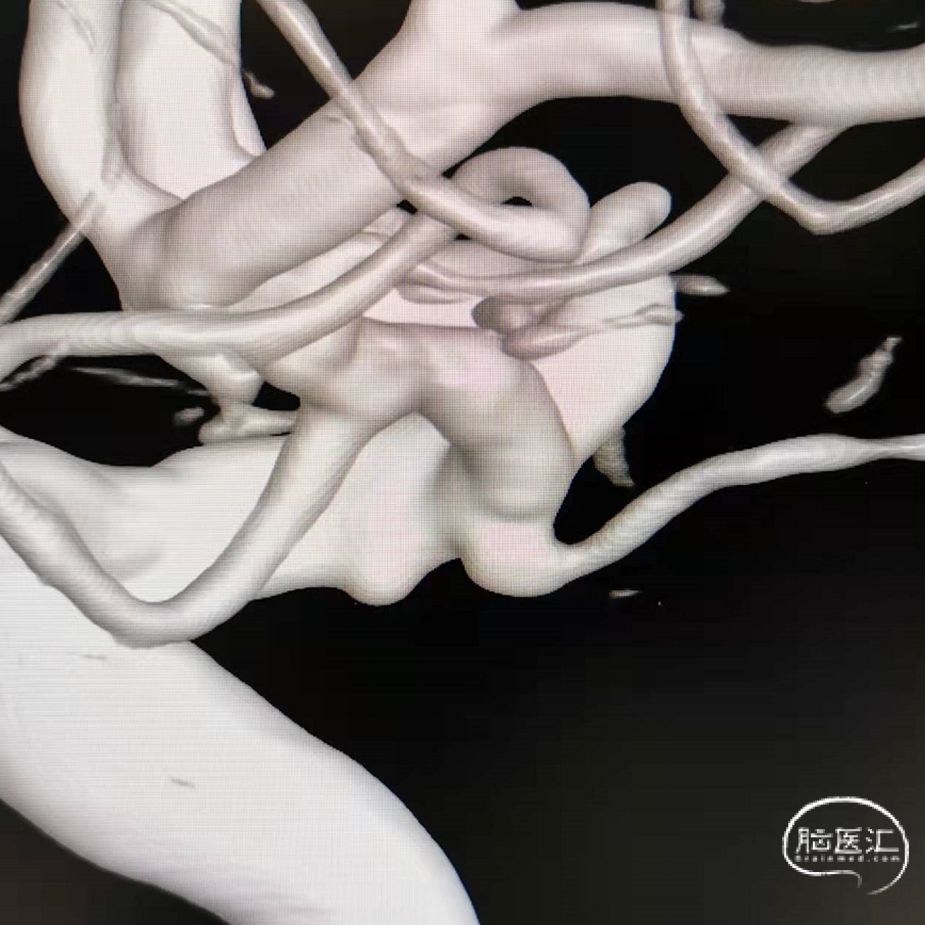

DSA三维重建

DSA:数值测量

破裂的真性脉络膜前动脉微小动脉瘤

脉络膜前动脉动脉瘤和真性脉络膜前动脉动脉瘤的鉴别,后者的位置距离脉络膜前动脉和颈内动脉的连接处有一段距离